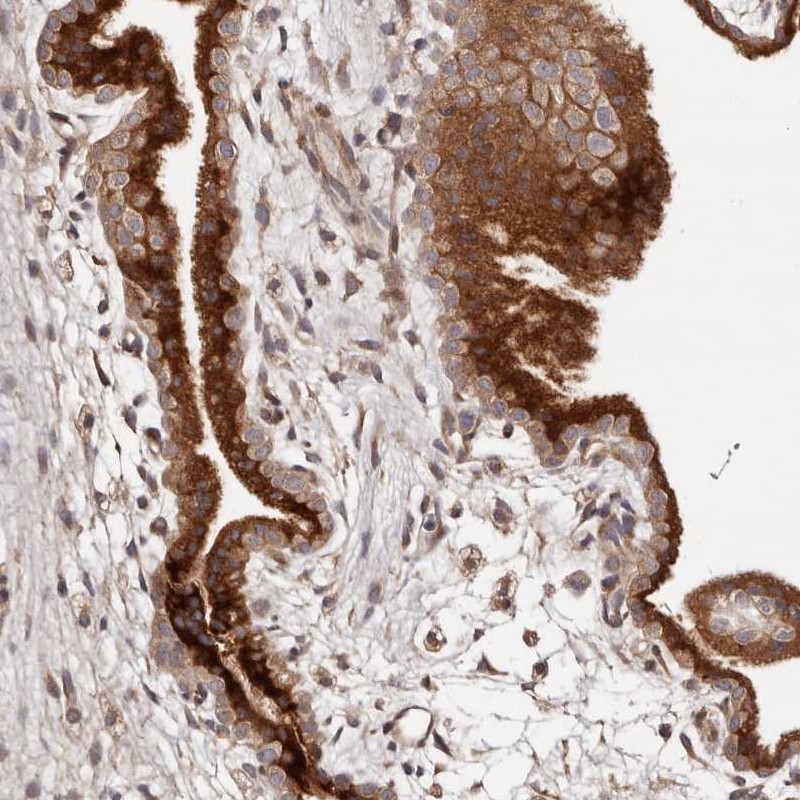

Immunohistochemical staining of human placenta shows cytoplasmic positivity in trophoblastic cells.